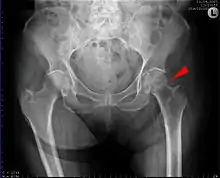

Subcapital fracture in a 92-year-old woman

X-rays of the affected hip usually make the diagnosis obvious; AP (anteroposterior) and lateral views should be obtained.